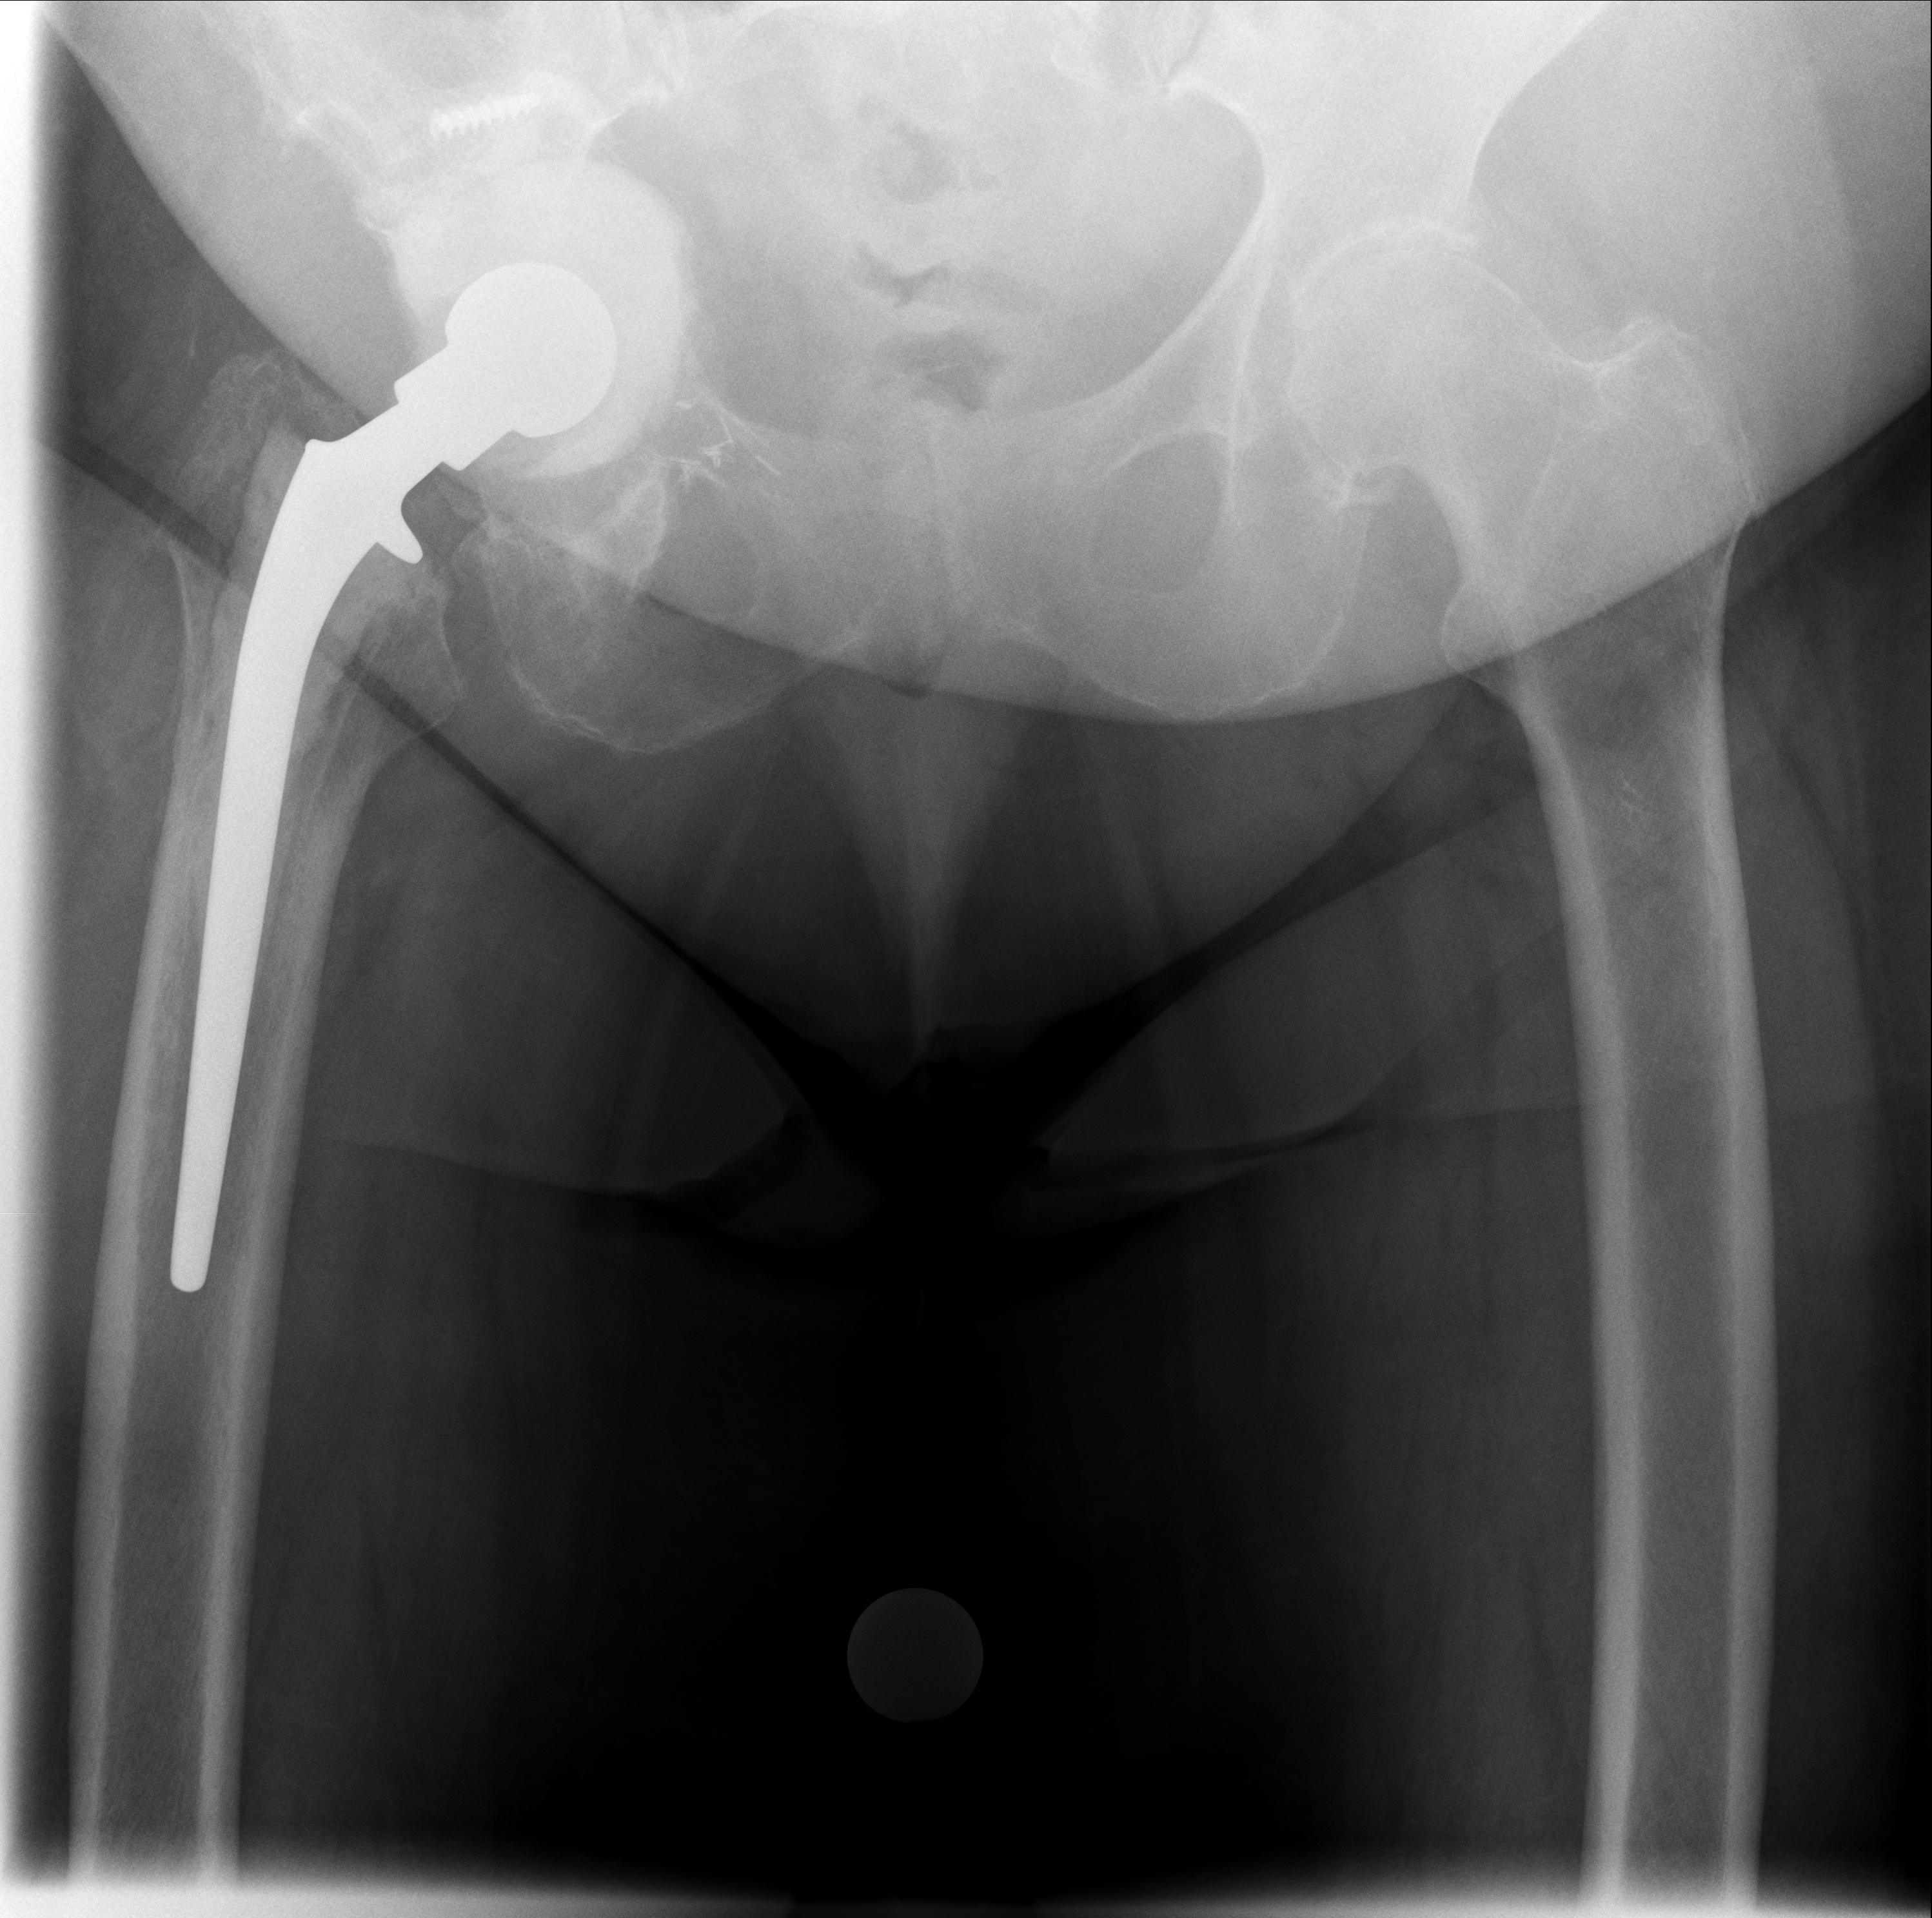

Bildvergleich: Behandlungsverlauf

Röntgenbilder im Verlauf: korrekte Lage → Luxation → neue TEP nach Wiedereinbau

07.10.2024 - Korrekt

Röntgen Oktober 2024

Prothesenkopf sitzt korrekt in der Pfanne

21.11.2025 - Luxiert

Röntgen November 2025

Prothesenkopf aus Pfanne luxiert

24.02.2026 - Neue TEP

Röntgen Februar 2026

Neue Hüft-TEP rechts nach Wiedereinbau

Akuter Befund: Hüftprothesen-Luxation

Vergleich der Röntgenbilder zeigt eine Luxation der Hüft-TEP rechts. Der Prothesenkopf ist aus der Pfanne ausgerenkt.

07.10.2024 - Prothese korrekt

Becken 2024

Prothesenkopf sitzt in der Pfanne

21.11.2025 - Luxation!

Becken 2025

Prothesenkopf luxiert nach medial/kaudal

24.02.2026 - Neue TEP!

Becken 2026